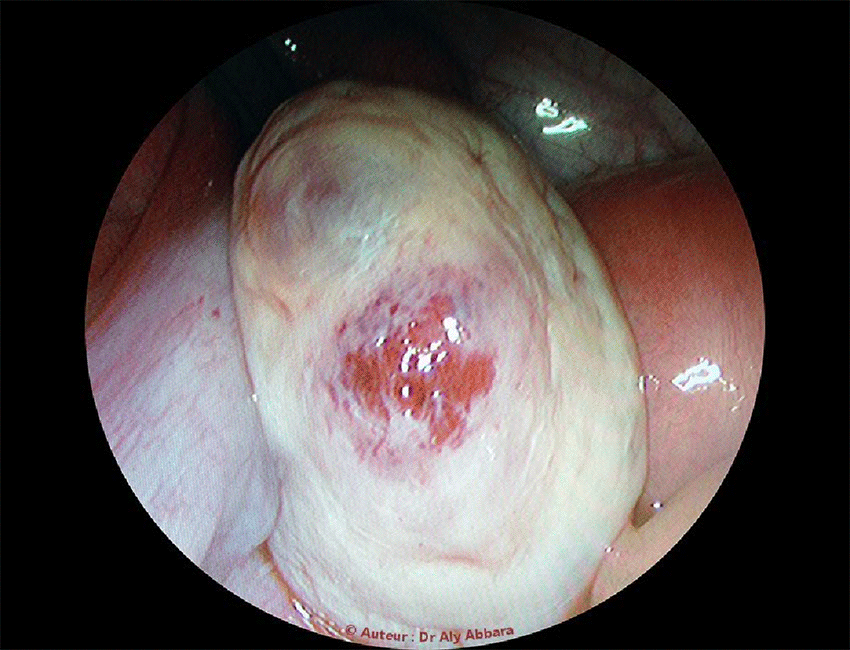

Cicatrice d'une

ovulation récente

à la surface de

l'ovaire

gauche

Cette image clinique montre une cicatrice récente à la surface de l'ovaire gauche : zone congestive avec écartèlement du cortex ovarien in-situ témoignant de sa déchirure lors d'une

ovulation

récente.